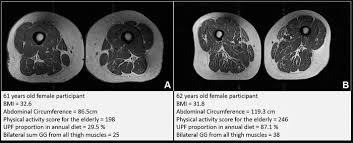

image: Representative axial T1-weighted spin-echo thigh MRI scans in (A) a 61-year-old female participant and (B) a 62-year-old female participant.